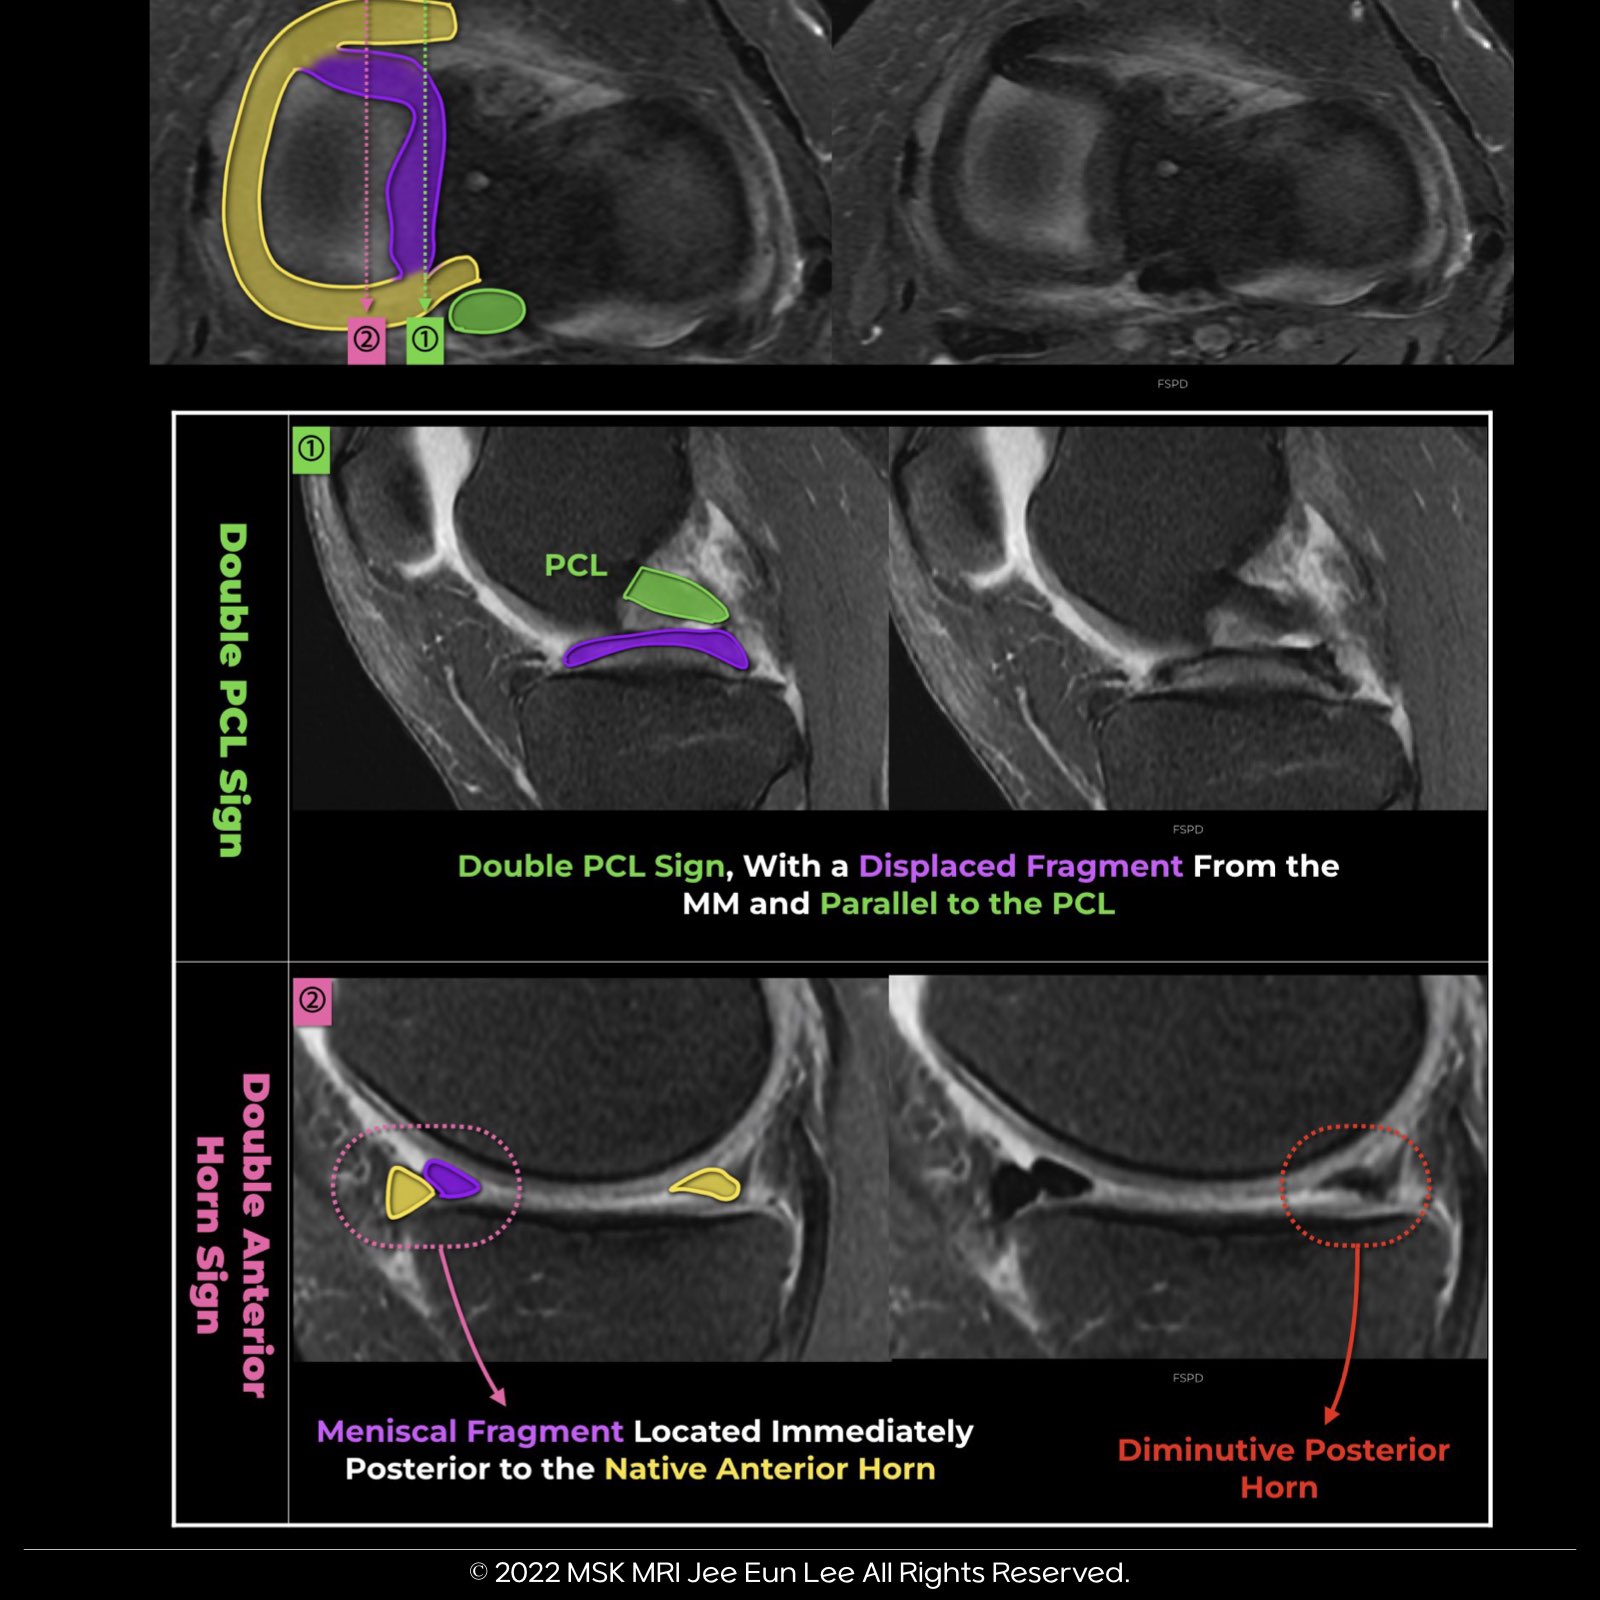

๐ง Double Posterior Cruciate Ligament (PCL) Sign:

Double posterior cruciate ligament (PCL) sign results from meniscal material in the notch, inferior and parallel to the PCL in the same sagittal plane.

The intact ACL serves as a barrier, preventing further lateral displacement of the meniscal segment.